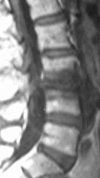

Delayed complications following lumbar spine fusion may occur amongst which is adjacent segment degeneration (ASD). Although interspinous implants have been successfully used in spinal stenosis to authors' knowledge such implants have not been previously used to reduce ASD in instrumented lumbar fusion. This prospective controlled study was designed to investigate if the implantation of an interspinous implant cephalad to short lumbar and lumbosacral instrumented fusion could eliminate the incidence of ASD and subsequently the related re-operation rate. Groups W and C enrolled initially each 25 consecutive selected patients. Group W included patients, who received the Wallis interspinous implant in the unfused vertebral segment cephalad to instrumentation and the group C selected age-, diagnosis-, level-, and instrumentation-matched to W group patients without interspinous implant (controls). The inclusion criterion for Wallis implantation was UCLA arthritic grade <II, while the exclusion criteria were previous lumbar surgery, severe osteoporosis or degeneration >UCLA grade II in the adjacent two segments cephalad to instrumentation. All patients suffered from symptomatic spinal stenosis and underwent decompression and 2-4 levels stabilization with rigid pedicle screw fixation and posterolateral fusion by a single surgeon. Lumbar lordosis, disc height (DH), segmental range of motion (ROM), and percent olisthesis in the adjacent two cephalad to instrumentation segments were measured preoperatively, and postoperatively until the final evaluation. VAS, SF-36, and Oswestry Disability Index (ODI) were used. One patient of group W developed pseudarthrosis: two patients of group C deep infection and one patient of group C ASD in the segment below instrumentation and were excluded from the final evaluation. Thus, 24 patients of group W and 21 in group C aged 65+ 13 and 64+ 11 years, respectively were included in the final analysis. The follow-up averaged 60 +/- 6 months. The instrumented levels averaged 2.5 + 1 vertebra for both groups. All 45 spines showed radiological fusion 8-12 months postoperatively. Lumbar lordosis did not change postoperatively. Postoperatively at the first cephalad adjacent segment: DH increased in the group W (P = 0.042); ROM significantly increased only in group C (ANOVA, P < 0.02); olisthesis decreased both in flexion (P = 0.0024) and extension (P = 0.012) in group W. The degeneration or deterioration of already existed ASD in the two cephalad segments was shown in 1 (4.1%) and 6 (28.6%) spines in W and C groups, respectively. Physical function (SF-36) and ODI improved postoperatively (P < 0.001), but in favour of the patients of group W (P < 0.05) at the final evaluation. Symptomatic ASD required surgical intervention was in 3 (14%) patients of group C and none in group W. ASD remains a significant problem and accounts for a big portion of revision surgery following instrumented lumbar fusion. In this series, the Wallis interspinous implant changed the natural history of ASD and saved the two cephalad adjacent unfused vertebra from fusion, while it lowered the radiographic ASD incidence until to 5 years postoperatively. Longer prospective randomized studies are necessary to prove the beneficial effect of the interspinous implant cephalad and caudal to instrumented fusion. We recommend Wallis device for UCLA degeneration I and II.